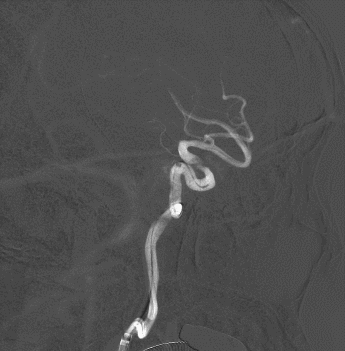

多角度造影明确左侧颈内动脉眼动脉段重度狭窄。

正位造影

侧位造影